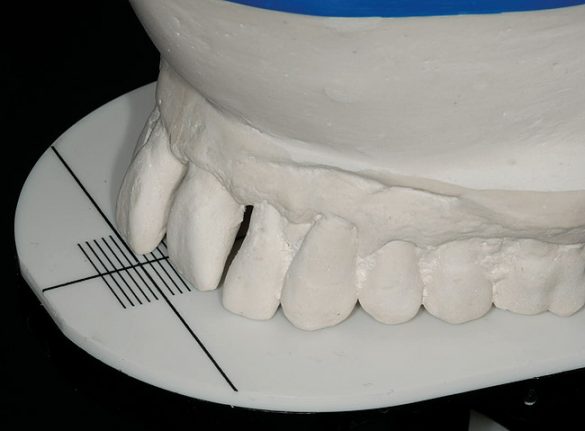

S-a conceput proteza provizorie imediată (fig. 6). Suprafaţa vestibulară a incisivului 2.1. era în poziţia orizontală dorită şi după scurtarea sa cu 3mm se afla şi în poziţia verticală dorită. Dintele 2.1. modificat a devenit apoi dintele „reper”, stabilind poziţia muchiei incizale. Laboratorului dentar i s-au oferit instrucţiuni pentru a înălţa dinţii superiori restanţi, menţinându-i la nivel cu poziţia scurtată a dintelui reper, cu întregirea planului ocluzal. Dinţii frontali inferiori au fost scurtaţi cu 2mm pe modelul diagnostic, stabilind poziţia muchiei incizale inferioare, iar laboratorul a fost instruit să închidă dimensiunea verticală de ocluzie cât era necesar pentru redobândirea contactului anterior dorit cu arcada superioară.

Proteza provizorie s-a apropiat extrem de mult de atingerea obiectivelor de ridicare a planului ocluzal pentru estetică şi repoziţionarea palatinală a incisivilor superiori (fig. 7). Încercarea de a eleva planul ocluzal a condus din punct de vedere estetic la situaţia în care planul ocluzal al protezei provizorii era superior faţă de acrilatul care acoperea tuberozitatea maxilară (fig. 8). În cursul perioadei de integrare, proteza provizorie a fost menţinută pe implanturile în curs de vindecare.